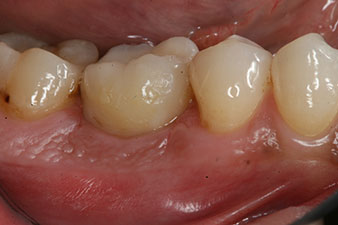

The final pictures show the screw-retained monolithic composite crown in place and the x-ray check (Fig. 9 and 10) (6).